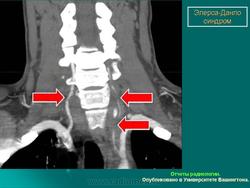

4. Кифосколиотический тип.

Наследуется по аутосомно-рецессивному типу. Основные диагностические критерии: генерализованная гипермобильность суставов, выраженная мышечная гипотония при рождении, прогрессирующий (с рождения) сколиоз, кифоз, хрупкость склер разрывы глазного яблока. Дополнительные диагностические критерии: хрупкость тканей, иногда атрофичные рубцы, склонность к кровоизлияниям, разрывы артерий, марфоноидный фенотип, микрокорнеа, рентгенологически выявляемая выраженная остеопения, положительный семейный анамнез ( в том числе больные сибсы).

Следует отметить, что наличие трех основных критериев является основанием для предположения диагноза и требует лабораторного обследования. Причем мышечная гипотония может быть очень выраженной и обусловливает задержку моторного развития. Выраженный сколиоз приводит к тому, что во второй-третьей декаде жизни больные теряют способность передвигаться самостоятельно. Хрупкость тканей глаза является причиной разрыва глазного яблока при малейшей травме. Согласно последним данным, тяжелые глазные осложнения встречаются гораздо реже, чем предполагалось ранее. При этом типе СЭД дефект в синтезе коллагена заключается в изменении фермента лизил-гидроксилазы, которая катализирует гидроксилирование боковых лизиновых цепей, необходимых для перекрестных связей между соседними коллагеновыми молекулами при формировании тройной спирали.